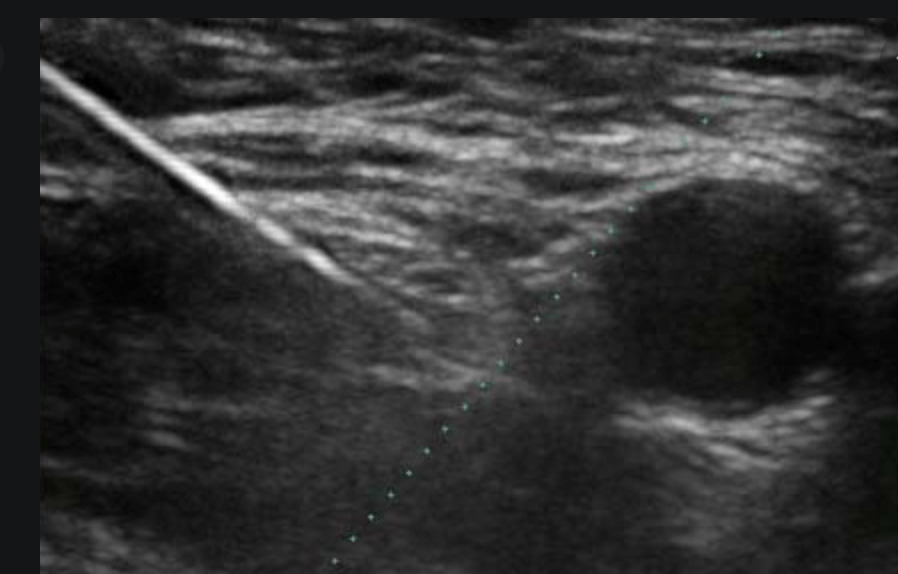

How to get started with regional anaesthesia

How to increase your learning curve when there are limited learning opportunities It seems that [...]